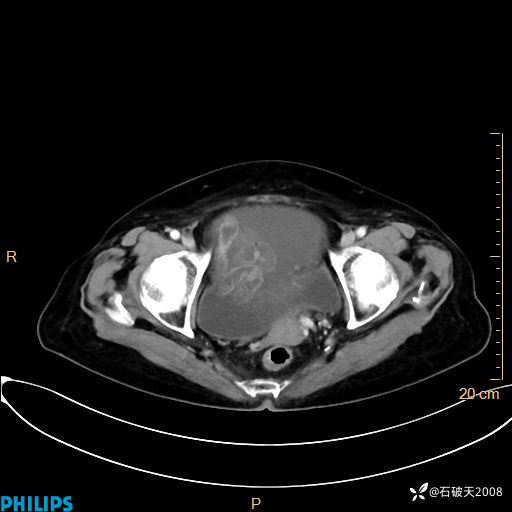

动脉期